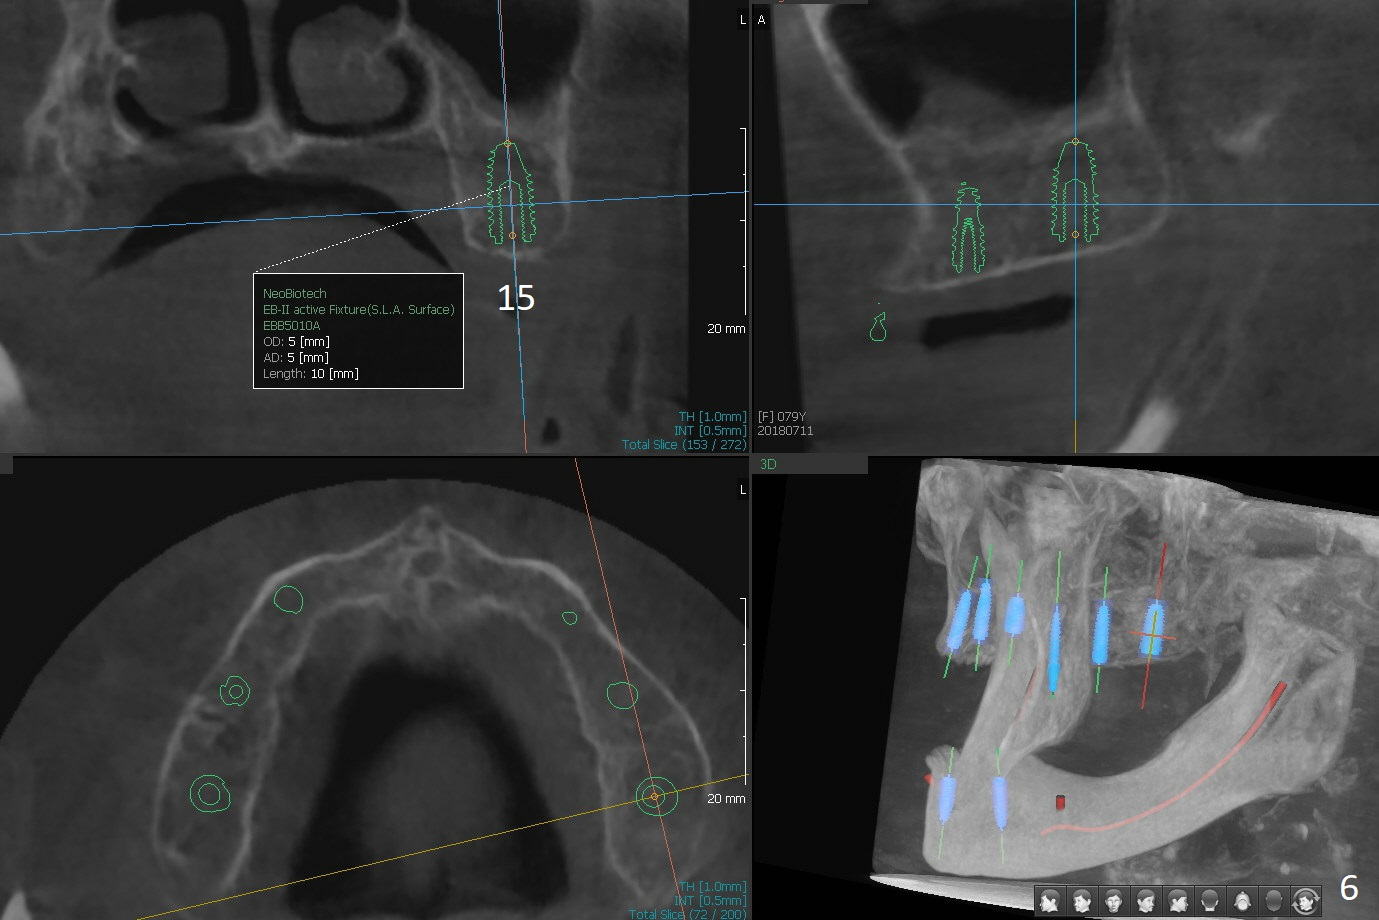

A 80-year-old woman wants to correct cross bite of complete dentures (Class II relationship). It seems that implant supported overdentures can make it possible (retention). Six implants will be placed in the maxillary canine and 2nd premolar and 2nd molar areas with surgical guide (Fig.1-6 (anterior ridge narrow)). Bone density is low. Prepare soft reline.